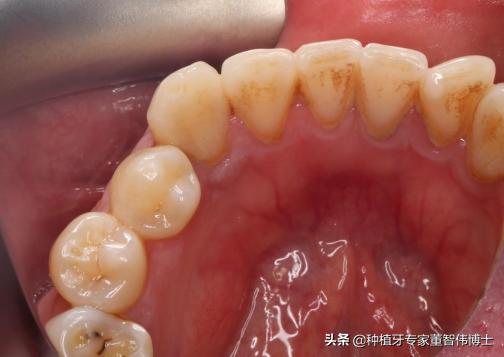

术前